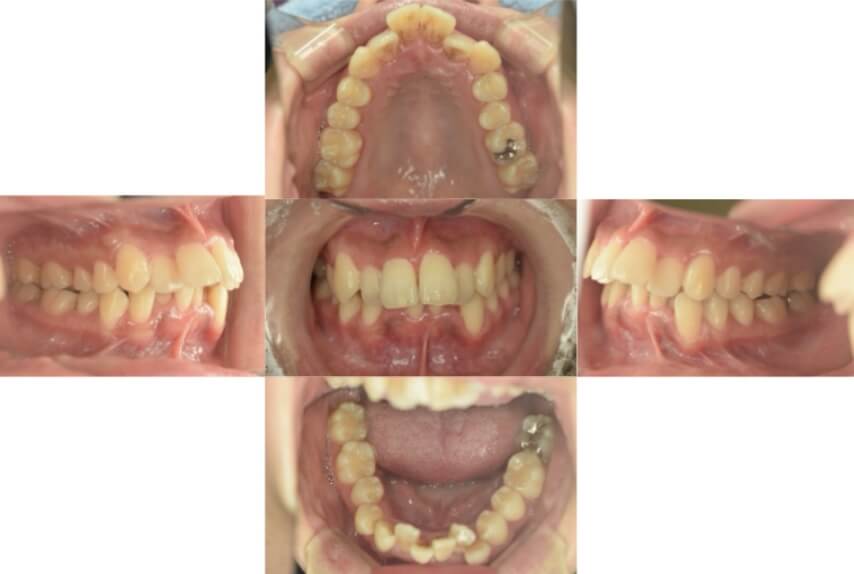

上下顎叢生(上下の前歯のガタガタ)のケースです。

装置はラビアル(上下表側)で、上下顎の小臼歯を4本抜歯を行っています。抜歯したスペースを使って、上下の前歯の後方移動と叢生(ガタガタ)の改善を行っています。

主訴 歯並びが悪く、舌を噛んでしまうのを治したい。

年齢・性別 27歳 男性

お住まいの地域 東京都大田区

治療方針 抜歯スペースを利用して上下前歯の叢生(ガタガタ)の改善

抜歯部位 上下顎左右第一小臼歯

使用装置 ラビアル(上下表側)、顎間ゴム

治療期間 3年1か月

治療回数 30回

BEFORE